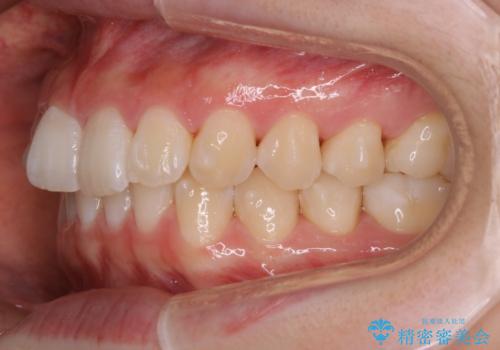

- 初診時、前歯のガタつきを主訴にご来院されました。

精密検査の結果奥歯の噛み合わせのズレからくる前歯のガタつきであることが分かり、患者様と相談した結果、全体をしっかりと治療することをご選択なさったので奥歯から動かして噛み合わせと見た目の両方を治す治療プランとなりました。

下顎の歯は幸いガタつきが少なかったため、下顎を基準とし構成する方針としました。